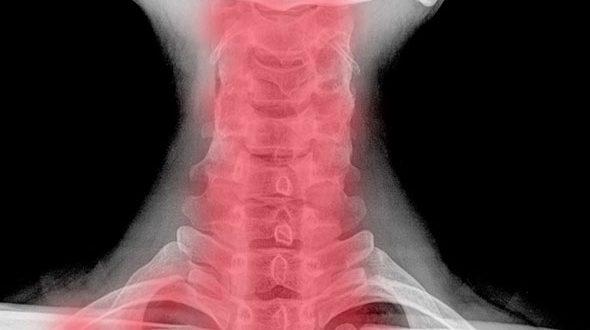

Radiografia gâtului poate arăta, de exemplu, excrescenţele osoase, care sunt semn clar de spondiloză sau cauze mai grave ale durerii şi rigidităţii: tumori, infecţii sau fracturi. CT-ul sau RMN-ul pot oferi acele informaţii importante despre nervi şi măduva spinării, dar şi despre oase sau discurile vertebrale, ce ajută la stabilirea clară a diagnosticului, fiind metode mai specifice de diagnostic.